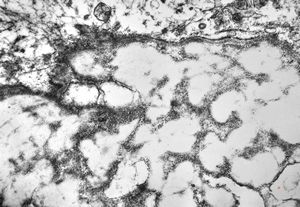

oral saprophytic bacterium